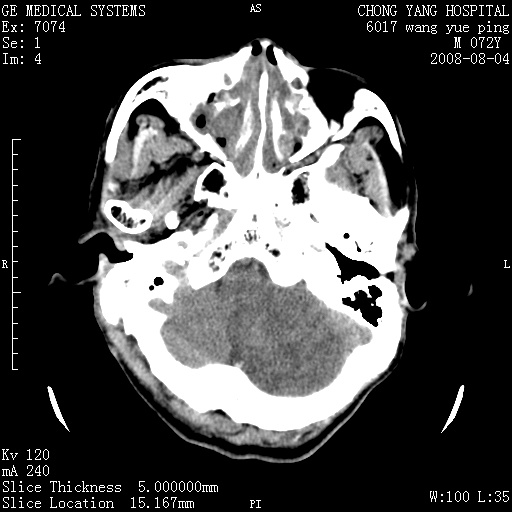

标题: CT14987:M72Y,头痛头昏,BP220/110. [打印本页]

标题: CT14987:M72Y,头痛头昏,BP220/110.

1)考虑左侧小脑脑梗塞。2)脑白质病。3)脑萎缩。4)双侧鼻腔新生物(息肉?)并阻塞性副鼻窦炎。

1.左侧小脑大面积梗塞;2.左侧基底节区腔梗;3.白质疏松;4.脑萎缩;5.慢性副鼻窦炎

小脑左侧病灶呈扇形分布,增强后未见明显瘤体样节结影,病变区未见强化。

支持:左侧小脑脑梗塞梗塞表现

另:脑白质病。脑萎缩。双侧鼻腔新生物(息肉?)并阻塞性副鼻窦炎。

1)考虑左侧小脑脑梗塞,建议治疗后复查除外其他,左基底节区腔隙性脑梗塞2)脑白质变性3)脑萎缩。4)双侧鼻腔新生物(息肉?)并阻塞性副鼻窦炎。